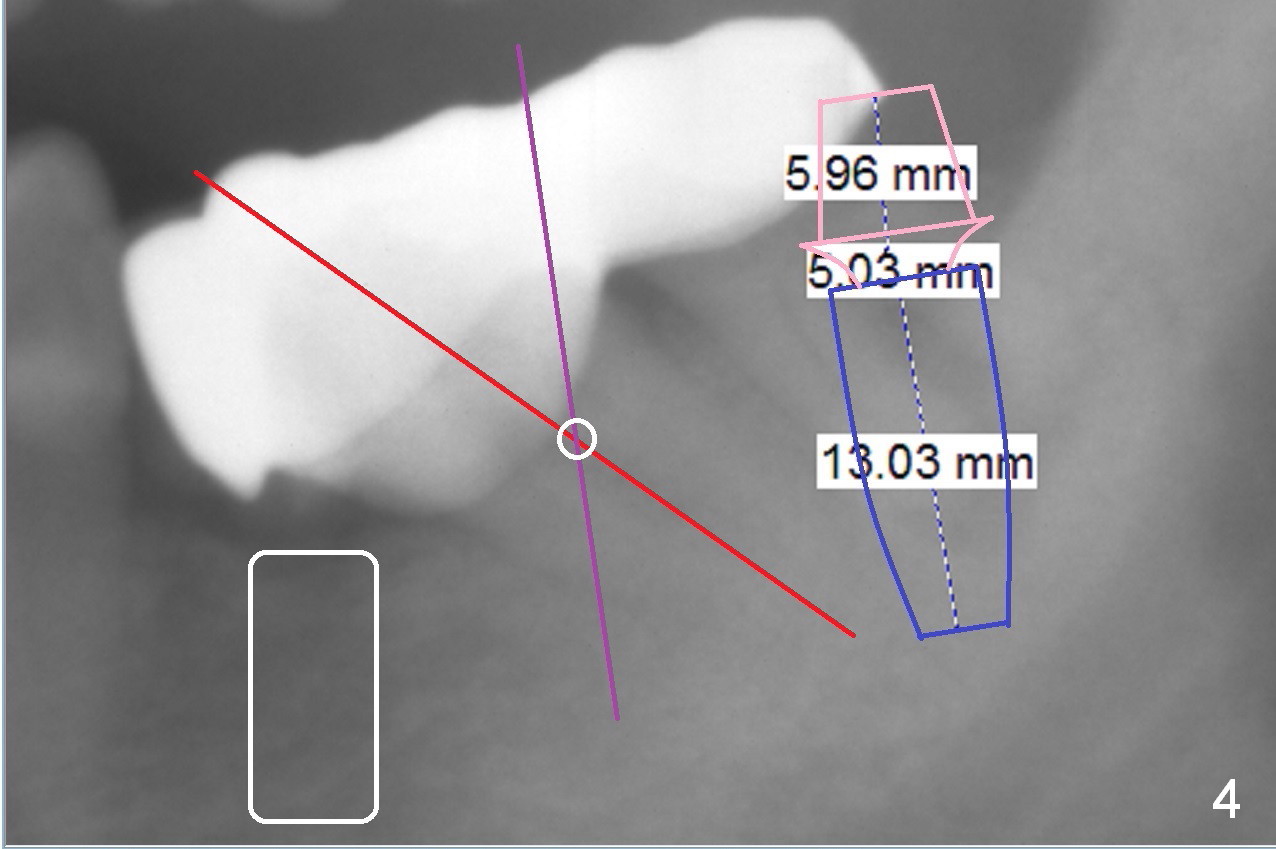

A 82-year-old man has pain in the lower left bridge. There is a buccal apical fistula associated with the tooth #17 (Fig.1). An immediate implant will be placed at #17 after bridge removal (Fig.2,3 blue). Once it osteointegrates, it will be used an anchorage (direct (instead of indirect), most efficient) to upright the tooth #18 (change the longitudinal axis from red line to purple one (Fig.4); white circle: center of resistance (rotation)). Then an implant will be placed at #19 (white rectangle).

Take Alginate impression and keep it moist. It will be used as a stent for temporization later on. After the tooth #17 is extracted with Clindamycin treatment, a FC dummy implant (5x9 mm) will be placed, followed by 6x4(2) mm abutment (Fig.3,4 pink). If there is severe vertical height issue, change to Magicore. Due to schedule conflict, prepare UF for this case instead.